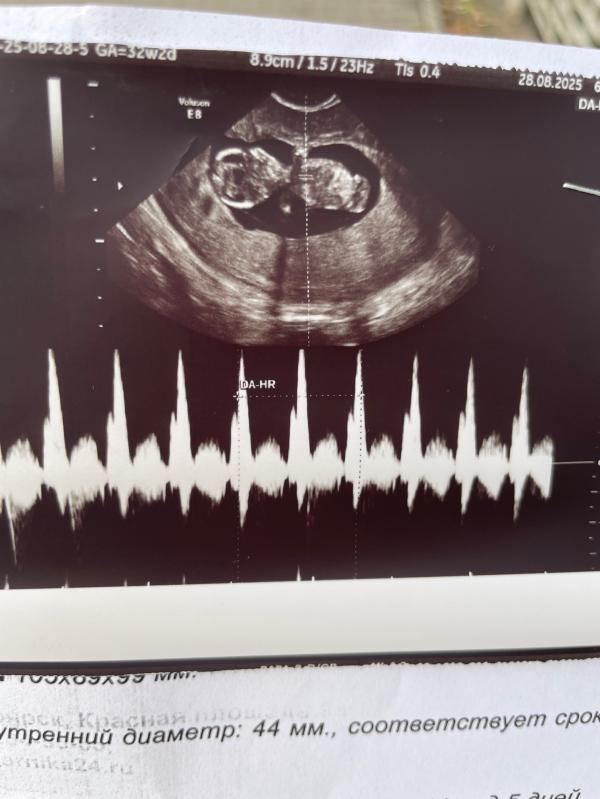

У малыша все отлично) Помахала ручкой и пустилась в пляс)

Наша любимая Эмилия, мы тебя ждем 🩷